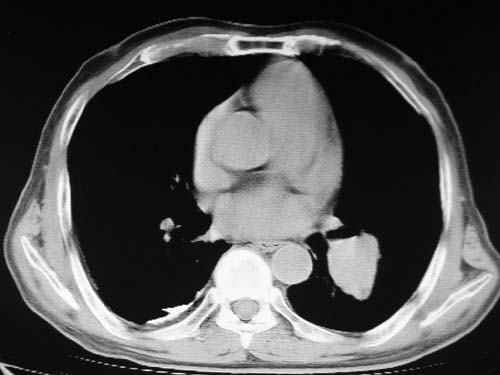

男,80岁

肺动脉段突出,左右肺门不等大,左肺门明显增大,肺动脉干及左肺动脉明显增宽,考虑先天性肺动脉狭窄瓣膜狭窄型。

)考虑肺动脉扩张,右心室增大,主动脉弓段正常位弓后段明显变小(不会是动脉导客未闭吧,不知患者有何症状病史)0。2)右肺上叶继发性肺结核。3)右侧胸膜增厚、钙化,左侧胸膜反应。